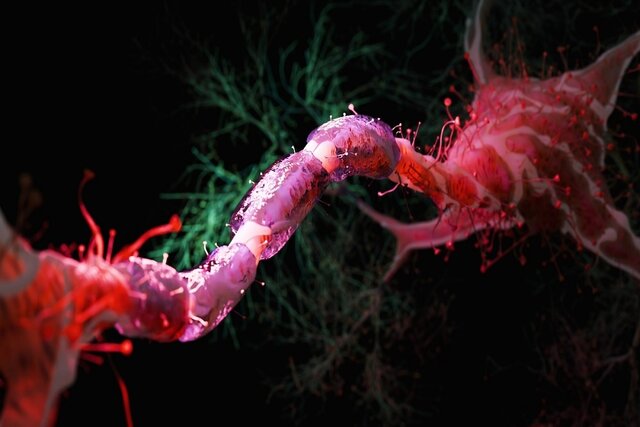

این ساختمان در هلند ساخته شده و با سفر به درون آن میتوان با بازدید از همه بخشها، از کارکرد درست یک بدن سالم آگاه شد و آموزش دید. ارتفاع این ساختمان که از نظر ظاهری پیکر انسانی نشسته است، 35 متر است.

این تصاویر عجیب و بی نظیری كه مشاهده می کنید مربوط به یك ساختمان واقع در كشور هلند است كه شبیه انسان ساخته شده و از تاریخ چهاردهم مارس 2008 برای بازدیدكنندگان فعال بوده است. بطوریکه با سفر به درون آن میتوان از تمامی قسمت ها و کارکرد درست یک بدن انسان سالم اطلاعات لازم را کسب کرد و در این تجربه جدید برای بازدیدكنندگان خصوصا دانشجویان رشته پزشکی این امکان فراهم شده بود تا با قسمتهای داخلی بدن انسان و نحوه فعالیتهای آنها از نزدیك آشنا شوند.

این بنای انسانی که از نظر ظاهری پیکر انسانی نشسته است، در كنار یك ساختمان شیشه ای با ارتفاع 35 متر بنا شده كه در جوار اتوبان A44 آمستردام به هاگو (Hague) قابل مشاهده است. گرچه این تصاویر شاید برای شما دوستان پرشین استار چندان جدید نباشد ولی آنچه مهم است اهمیت آموزش و ایجاد انگیزه برای سهولت در شناخت و درک بهتر ساختمان پیچیده و اسرار آمیز بدن انسان نسبت به نیاز محققین و دانش اندوزانی است که مایلند به گوشه ای از اسرار عظمت خلقت خداوند که همان اشرف مخلوقات است دست یابند.